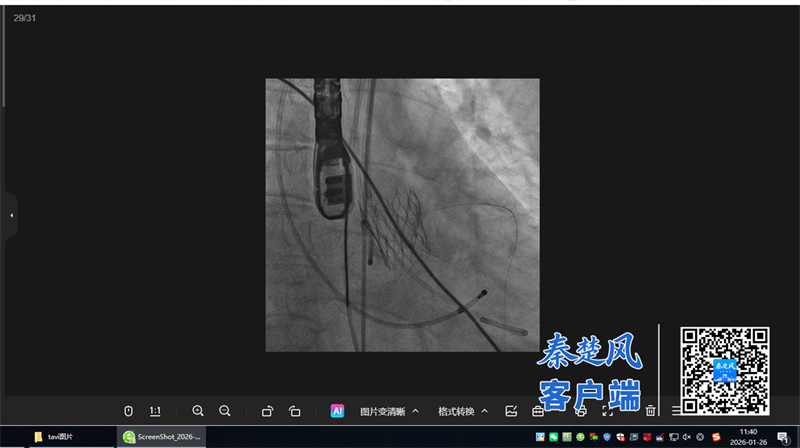

面对这一复杂病例,十堰市人民医院心血管内科3病区谭利国主任领衔的心脏介入团队,秉持严谨负责的态度,组织心胸外科、超声影像科、麻醉科、重症医学科(ICU)、内分泌科等进行了深入的多学科联合会诊(MDT)。 团队全面评估患者情况,最终为她“量体裁衣”,确定了目前全球领先的微创治疗方案——经导管主动脉瓣置换术(TAVR)。该技术无需切开胸骨,避免了传统手术的巨大创伤与漫长恢复期。

手术仅在患者大腿根部进行微创穿刺,通过血管路径将人工瓣膜精准输送至心脏病变处并释放,体表几乎不留痕迹。在多学科团队的精密协作与全程护航下,手术顺利完成,术后即刻效果显著。复查心脏彩超显示:原先严重的主动脉瓣狭窄已完全解除,新植入的瓣膜启闭良好,血流恢复通畅。